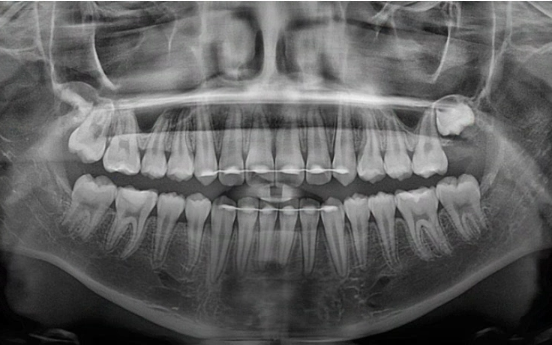

24.07

그리고 추가장치를 4달간 더 낀 후의 모습입니다.

중심선은 잘 맞아졌습니다.

교합도 좋습니다.

23.08~24.07

무엇보다 한쪽의 3급 어금니 교합관계는 1급이 되었습니다.

뿌리 평행도도 좋습니다.